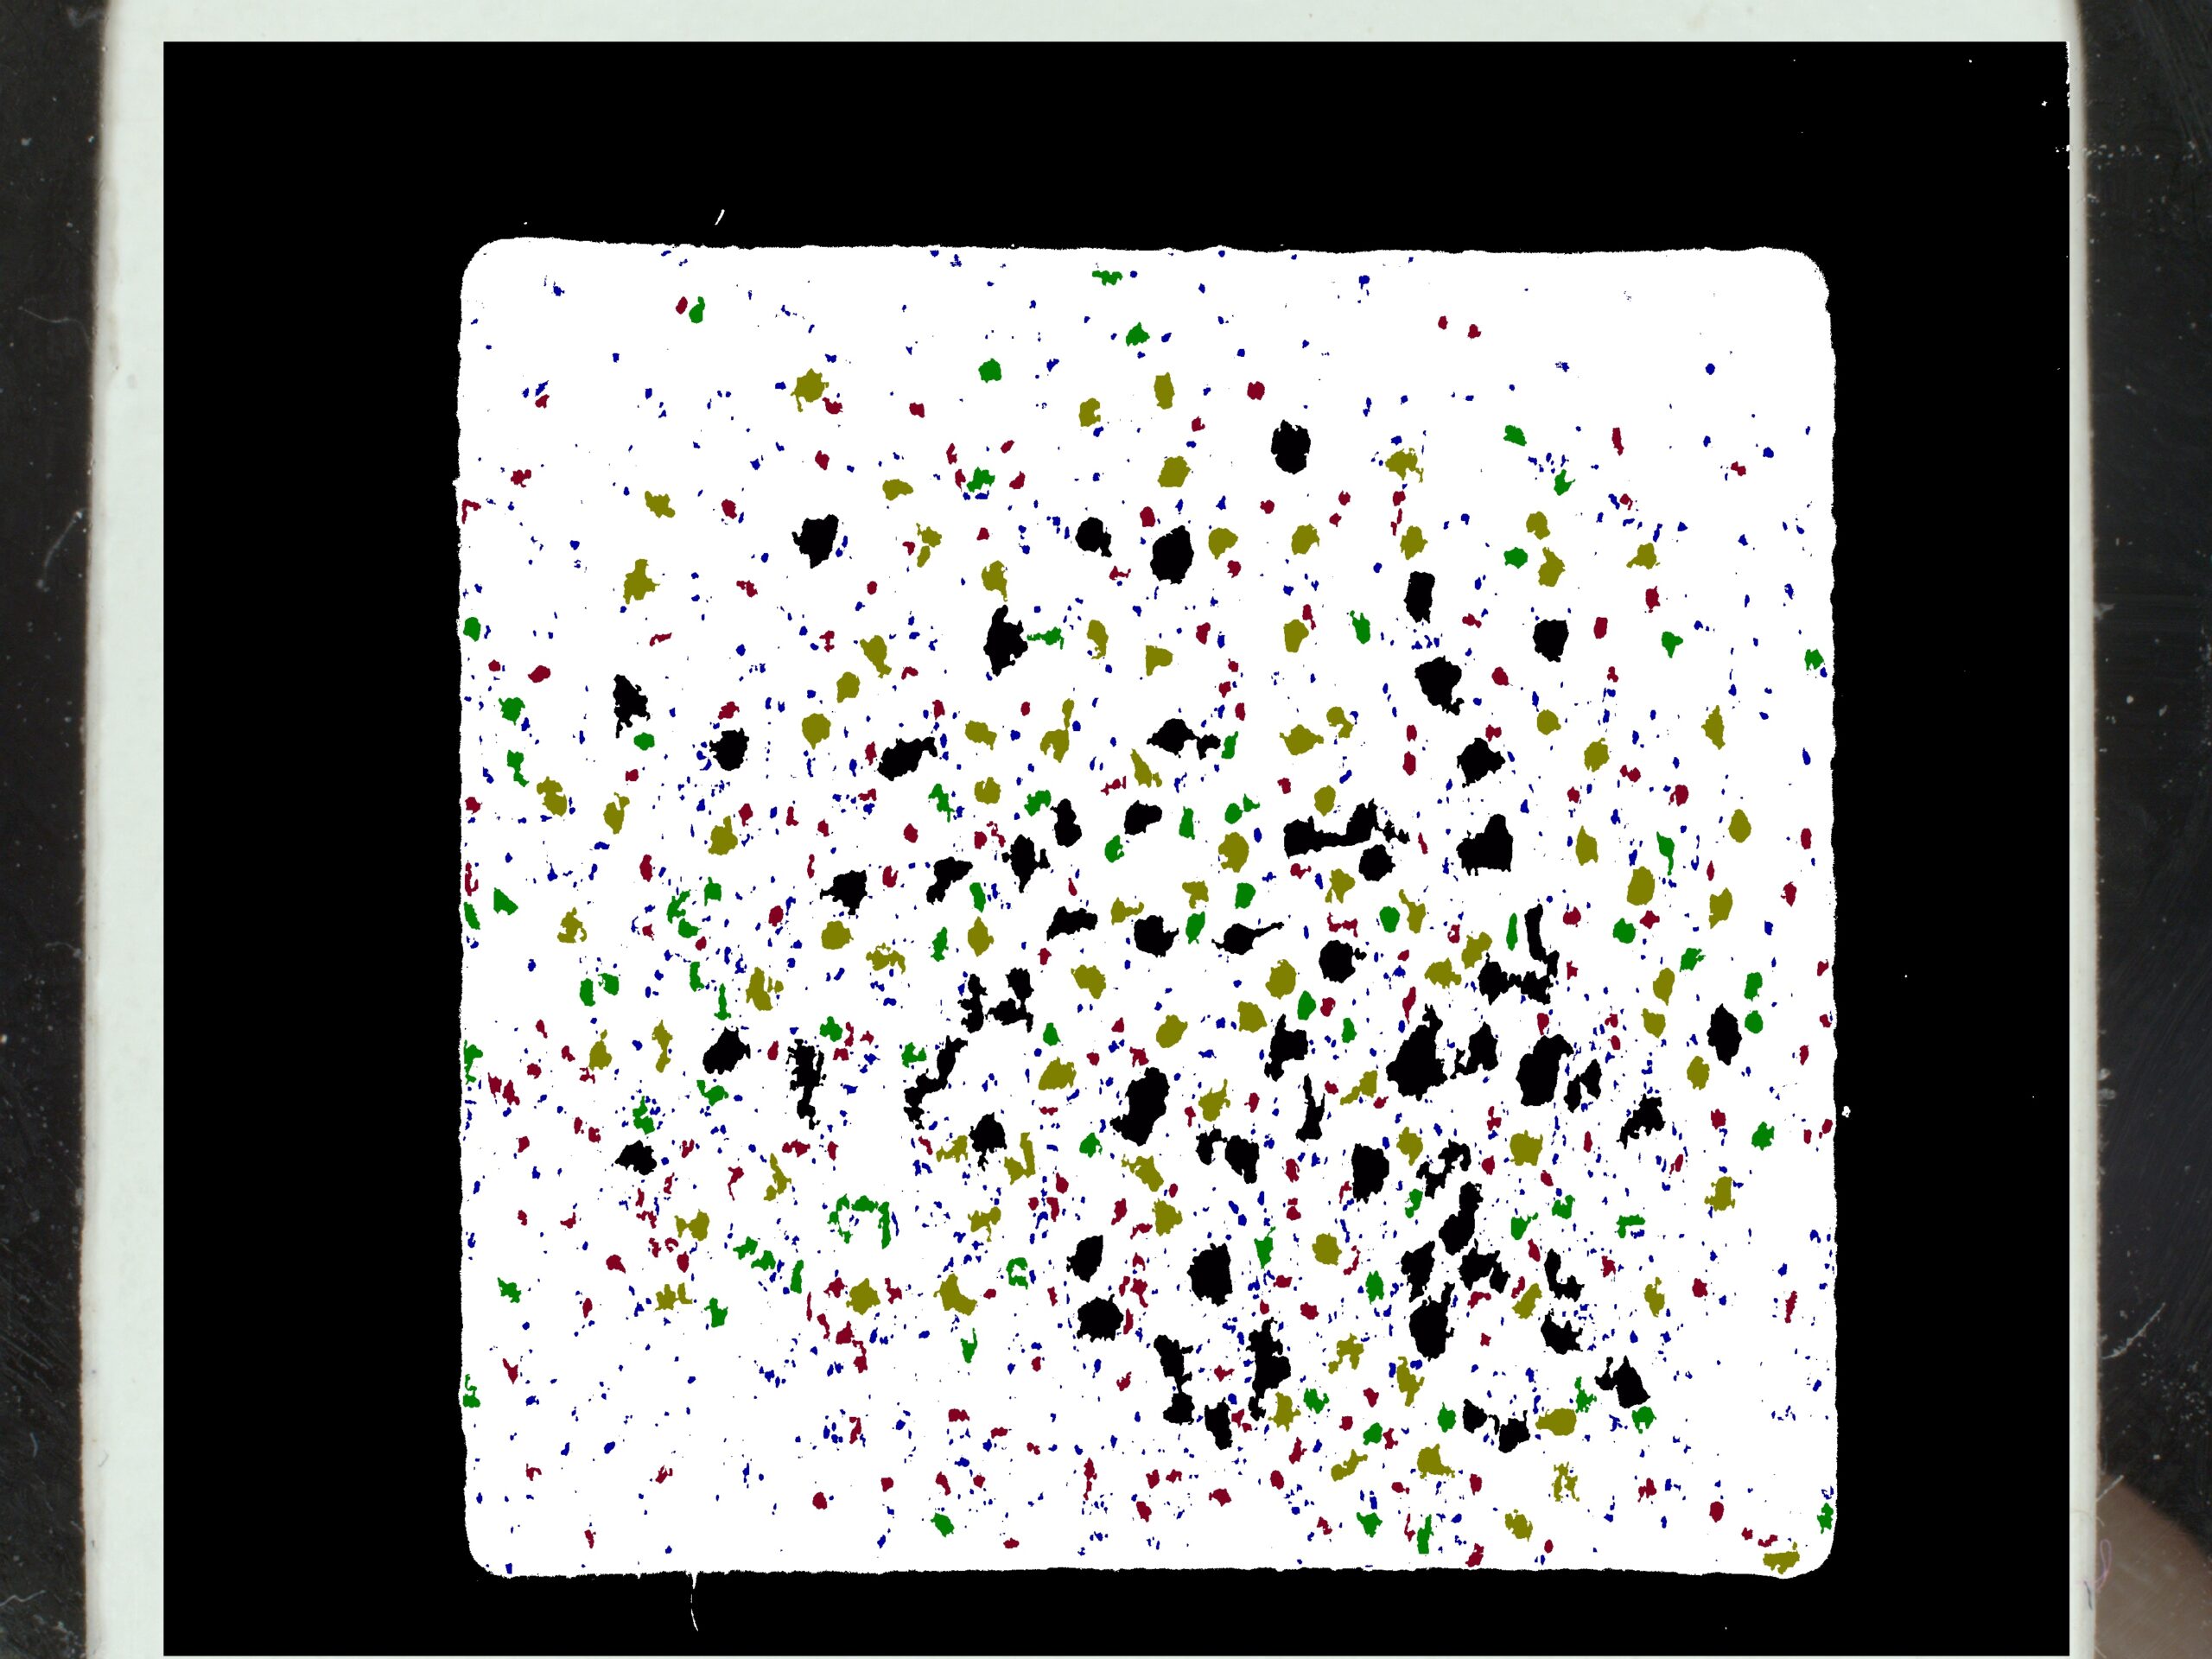

Évaluation de l’acné avec la mesure des points noirs

Les points noirs sont des amas de sébum produits par les glandes sébacées et par des dépôts de kératine obstruant les pores. Avec l’augmentation de la production de sébum sur les peaux à tendance acnéiques, il est donc courant d’être confronté à l’apparition de points noirs.

Le C-Cube permet de mesurer le nombre de points noirs et le diamètre moyen. Son champ de vision est constant et calibré, cela signifie que la surface de la photo est toujours la même (1.92cm²). La densité est donc obtenue en divisant le nombre de pores par la surface de 1,92 cm².

Analyse des pores

La production excessive de sébum peut avoir une incidence sur la taille des pores. Ces derniers peuvent se dilater. Grâce à ses mesures dimensionnelles fiables et son calibrage métrique, le C-Cube peut détecter le nombre de pores et les mesurer, en 2D et en 3D.

En 2D, cela consiste en l’analyse des couleurs, suivie par l’identification des formes pour éliminer d’autres objets et conserver uniquement les pores. Les résultats consistent en des images traitées en noir et blanc. Vous obtenez aussi une feuille de calcul avec la zone médiane, le diamètre médian et la densité des pores de chaque image.

Image source Image traitée